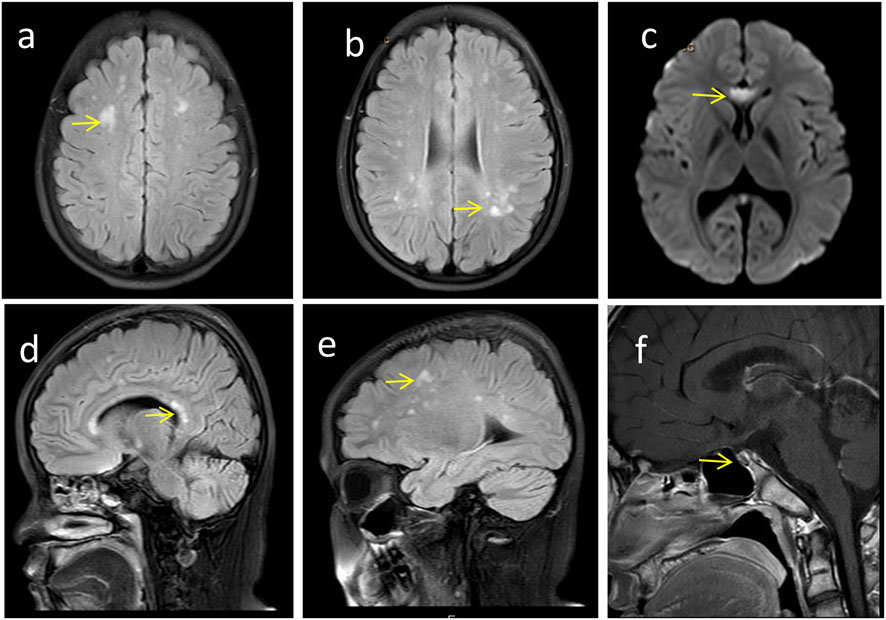

FIGURE 3

Craniocerebral imaging findings of the proband. (a-e) Brain MRI reveals high-signal white matter lesions (→ indicated), which involve the bilateral centrum semiovale, periventricular regions, as well as the genu and splenium of the corpus callosum. (f) Enhanced MRI of the pituitary gland demonstrates pituitary atrophy (→ indicated).

Follow-up at 18 years of age, the proband’s height was 158 cm (<10th percentile) and weight was 60 kg (between the 50th and 75th percentile). Physical characteristics included thick eyebrows, sparse scalp hair, trichomegaly, abnormal secondary sexual characteristics (micropenis, absent Adam’s apple, and absence of pubic and axillary hair), gait instability with frequent falls, dyspraxia (inability to carry basins without spilling), and impaired coordination (inability to maintain a single-leg stance) (Figure 2b). The neurological physical examination revealed no obvious abnormalities. However, a comprehensive neurophysiological assessment (including electroencephalogram, and visual evoked potentials) could not be completed as the patient and the family declined these tests. Cranial MRI (Figures 3a–e) showed T2-WI/T2-FLAIR hyperintense white matter lesions (Fazekas Ⅱ) in the bilateral centrum semiovale, periventricular regions, and genu/splenium of the corpus callosum. Callosal lesions appeared slightly hypointense on T1WI and hyperintense on DWI. Pituitary MRI with contrast (Figure 3f) revealed a sagittal height of 2.5 mm, consistent with pituitary atrophy.

Neurological and imaging abnormalities are also reported in PNPLA6-related disorders, including white matter signal changes, pituitary and cerebellar atrophy, and empty sella turcica. These may arise from loss of NTE function, leading to endoplasmic reticulum damage, vacuolation of nerve cell bodies, and abnormal reticular aggregates in the nervous system. NTE plays a crucial role in maintaining intracellular phospholipid homeostasis. Therefore, PNPLA6 variants may cause neurodegeneration via NTE dysfunction (Topalogl et al., 2014; Akassoglou et al., 2004). In our proband, cranial MRI showed hyperintense white matter signals involving the bilateral centrum semiovale, periventricular areas, and corpus callosum (genu and splenium), along with pituitary atrophy. White matter changes may underlie gait and balance impairments, while pituitary atrophy likely contributes to hormone deficits.